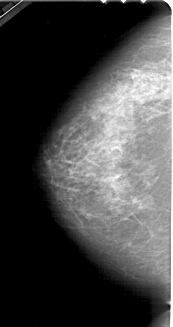

Digital Database for Screening Mammography

Volume: benign_05 Case: A-1491-1

A_1491_1.LEFT_MLO

LEFT_MLO LINES 5491 PIXELS_PER_LINE 2881 BITS_PER_PIXEL 12 RESOLUTION 43.5 NON_OVERLAY

LEFT_CC LINES 4891 PIXELS_PER_LINE 2581 BITS_PER_PIXEL 12 RESOLUTION 43.5 NON_OVERLAY